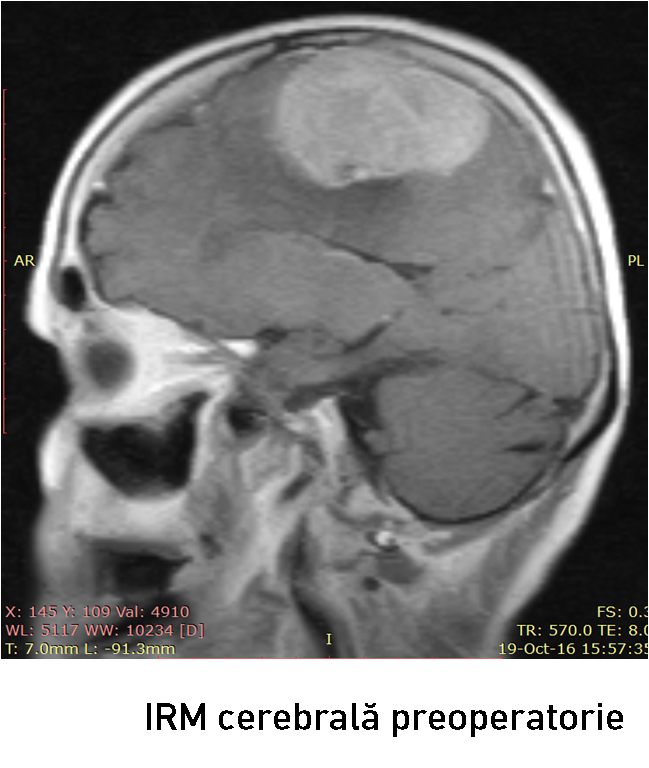

Examenul neuroimagistic prin IRM a stabilit prezența unei formațiuni tumorale intracraniene extraaxiale pe stânga (6

Examenul neuroimagistic prin IRM a stabilit prezența unei formațiuni tumorale intracraniene extraaxiale pe stânga (6

6 x 37 x 45 mm)la nivelul parasagital (1/3 medie a SSS) ce comprima regiunea precentrală și postcentrală stângă (fig. 1-2). Formațiunea de volum era atașată de sinusul sagital superior, de coasa creierului și capta intens substanța de contrast – suspect pentru un meningiom parasagital voluminos. Luând în considerație volumul leziunii tumorale, se impunea realizarea tratamentului neurochirurgical.